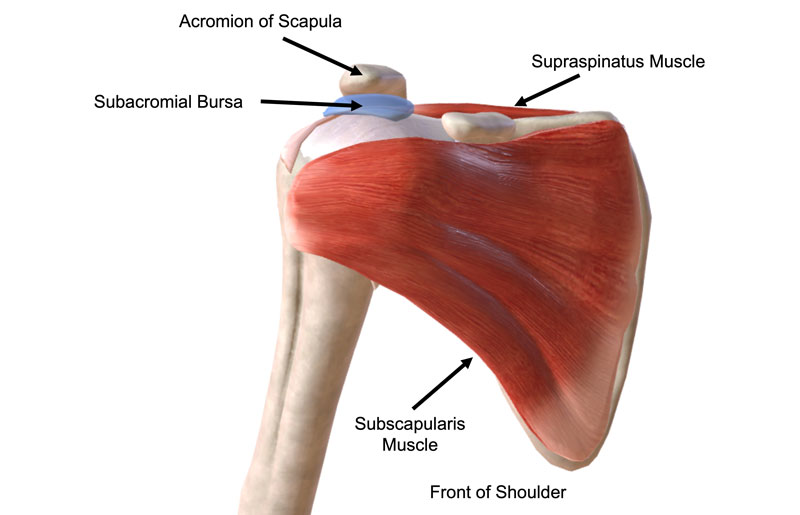

Фотографии мышц ротаторной манжеты плеча